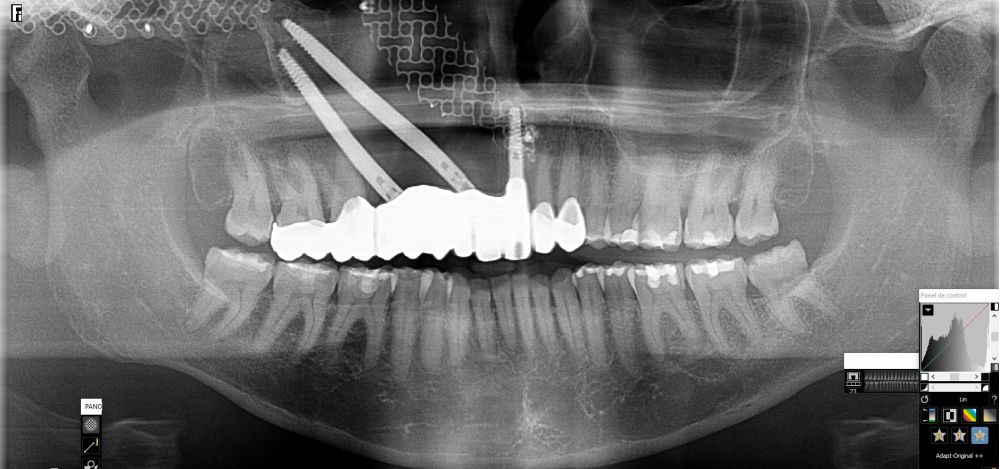

Bajo anestesia general, se realizó la resección quirúrgica junto con la fijación de dos placas preformadas y colocación simultánea de dos implantes cigomáticos y un implante endoóseo en posición del 2.1 (Figuras 5 y 6). Debido a la presencia de márgenes quirúrgicos comprometidos en el informe anatomopatológico, se indicó la administración de radioterapia adyuvante. Por este motivo, se decidió realizar un puente provisional dentosoportado de 1.7 a 2.3 (Figura 7) para mejorar la situación estética y funcional de la paciente durante todo el proceso y evitar un colapso de los tejidos blandos por la radioterapia. Para ello, se tallaron los molares (1.7, 1.6) e incisivo lateral y canino (2.2, 2.3), y se fabricó un puente fresado en polimetilmetacrilato (PMMA) con refuerzo metálico (Figuras 8 y 9).

Una vez finalizada la radioterapia, la paciente se encontraba libre de enfermedad. Por lo que se procedió a la restauración definitiva implantosoportada. Tras la segunda fase, se colocaron dos pilares transepiteliales Multiunit Ò rectos y un pilar Multunit Ò angulado de 17º (Figura 10).